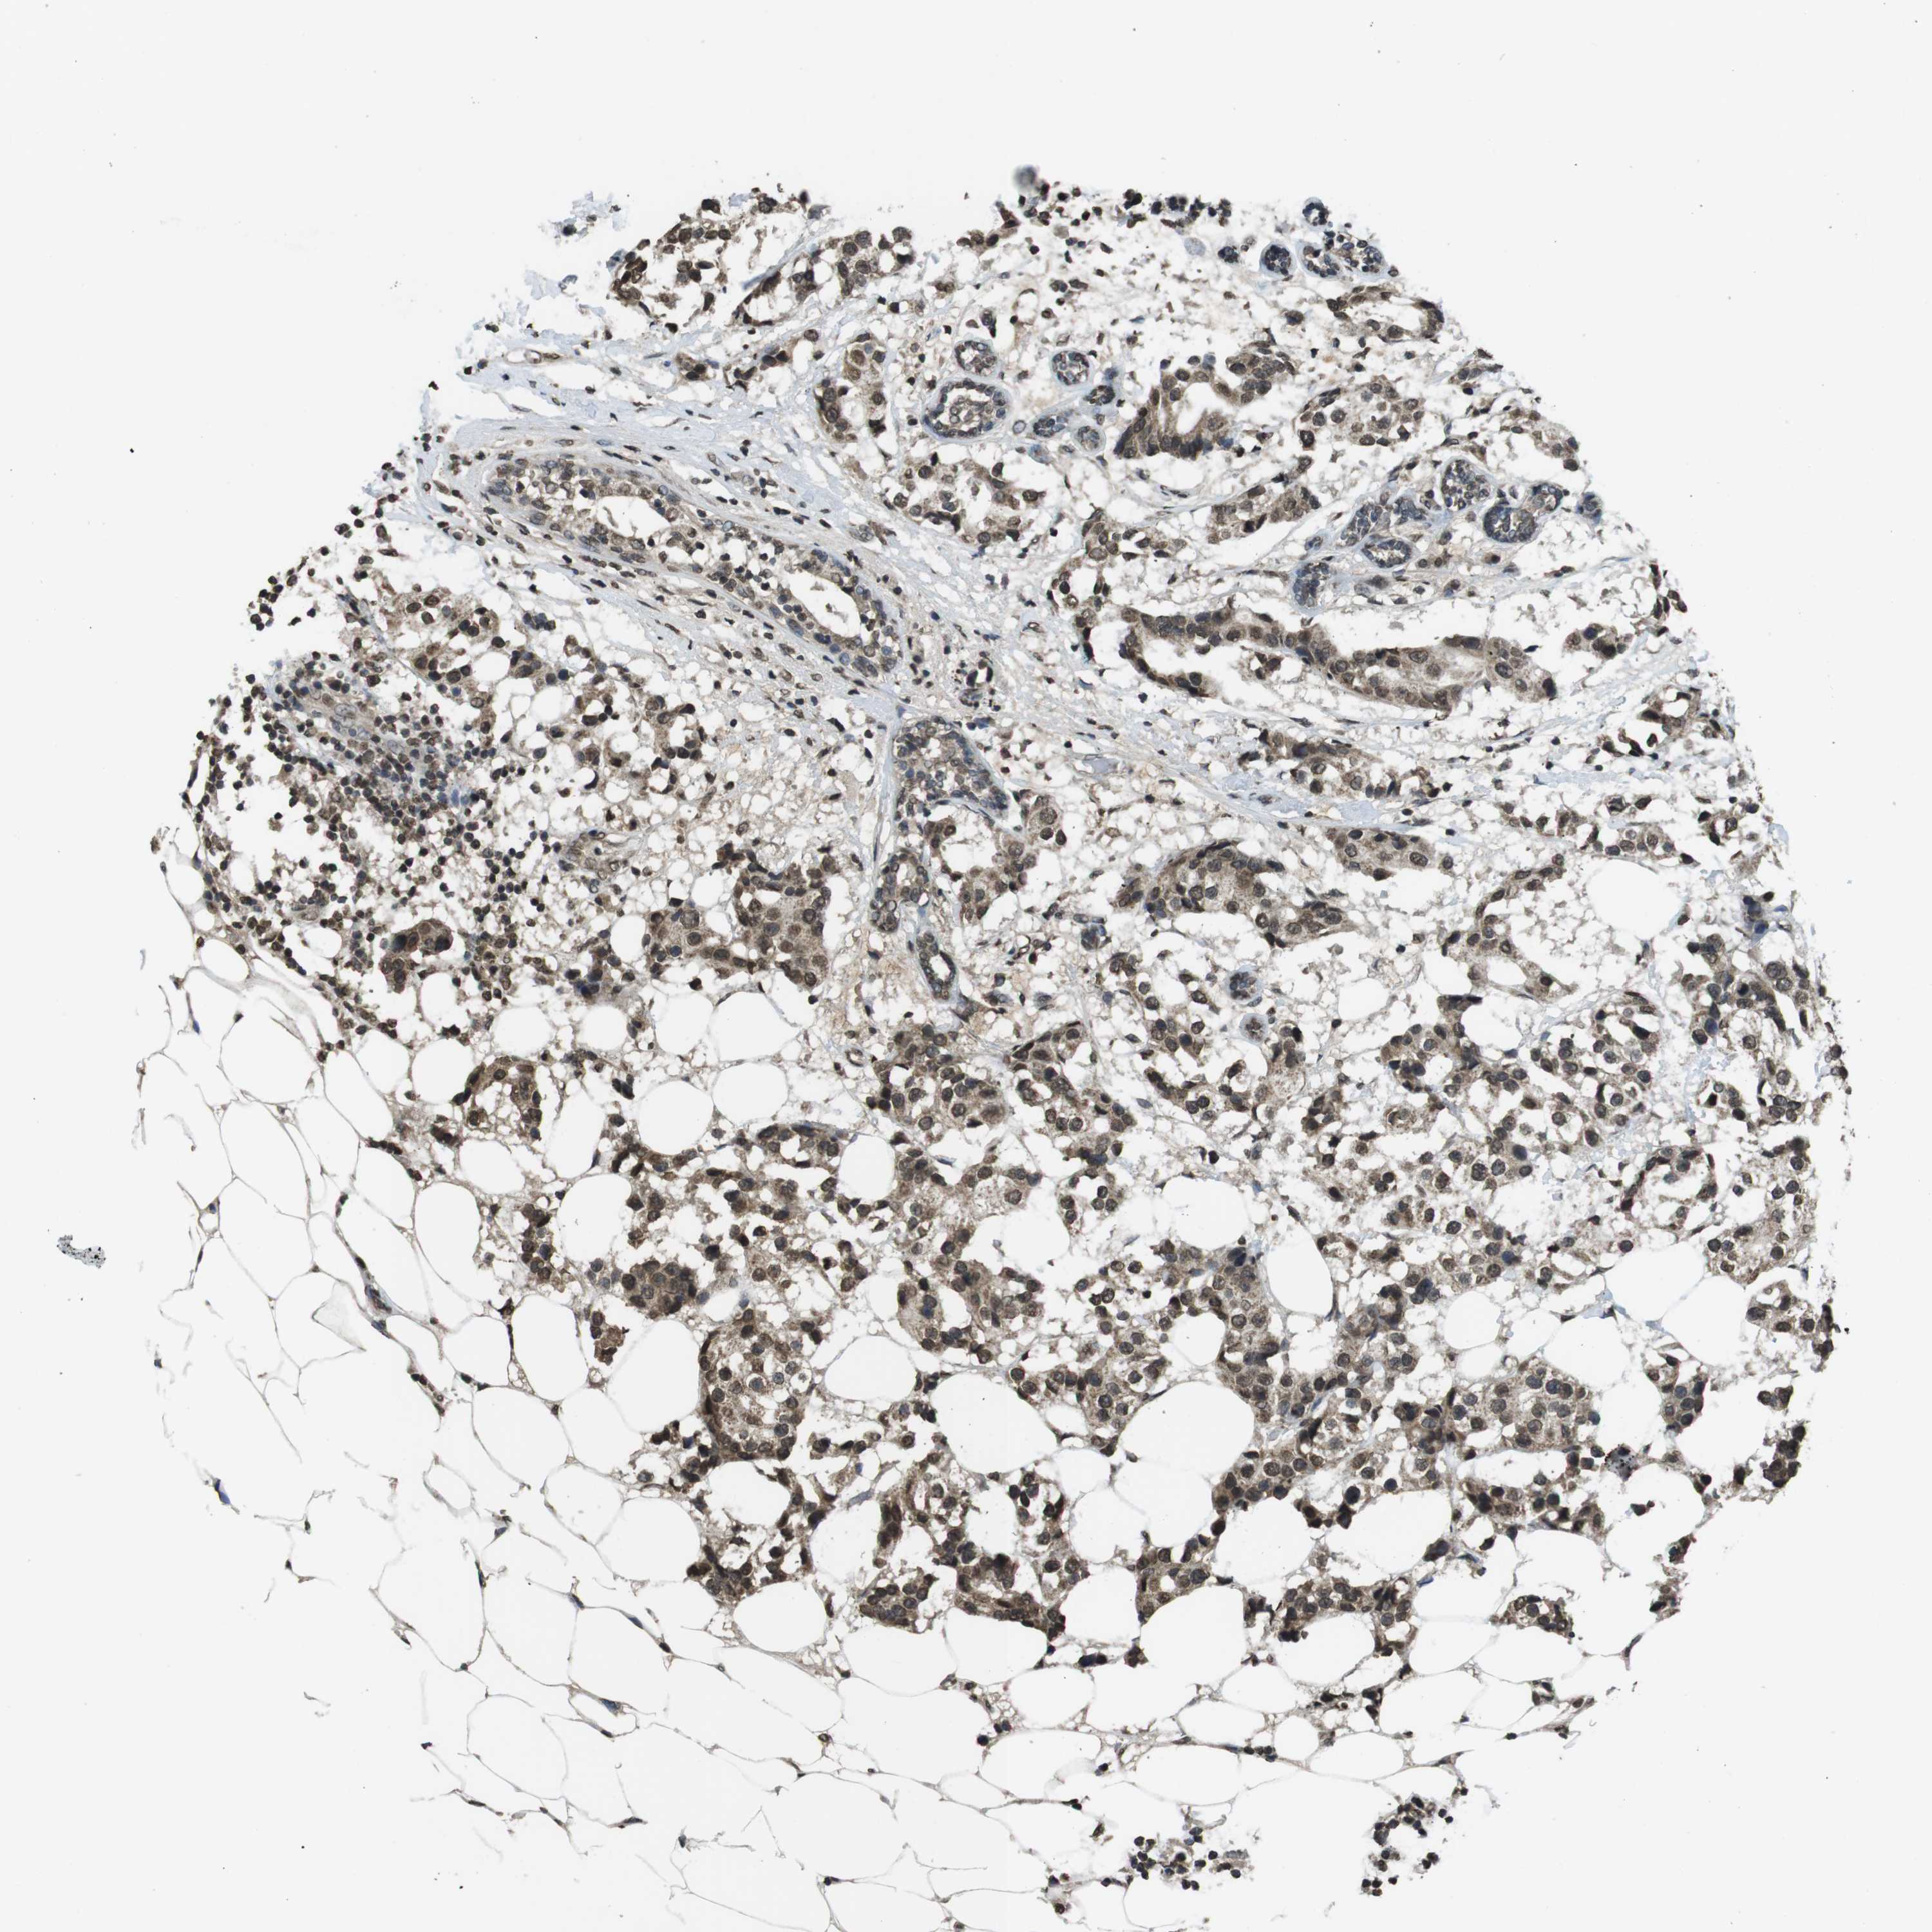

CANCER BREAST CANCER Show tissue menu

BRCA TCGA BRCA VALIDATION PROTEIN EXPRESSION